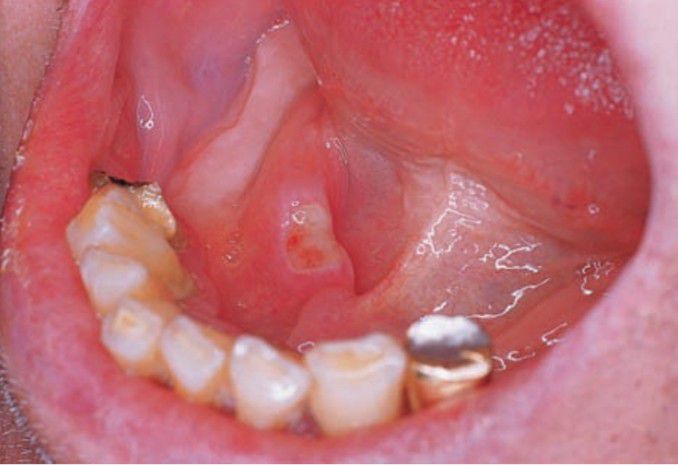

Minor aphthous ulcer (floor of mouth)

This type usually appears as a single, painful, oval ulcer that is less than 0.5 cm in diameter, covered by a yellow fibrinous membrane and surrounded by an erythematous halo.